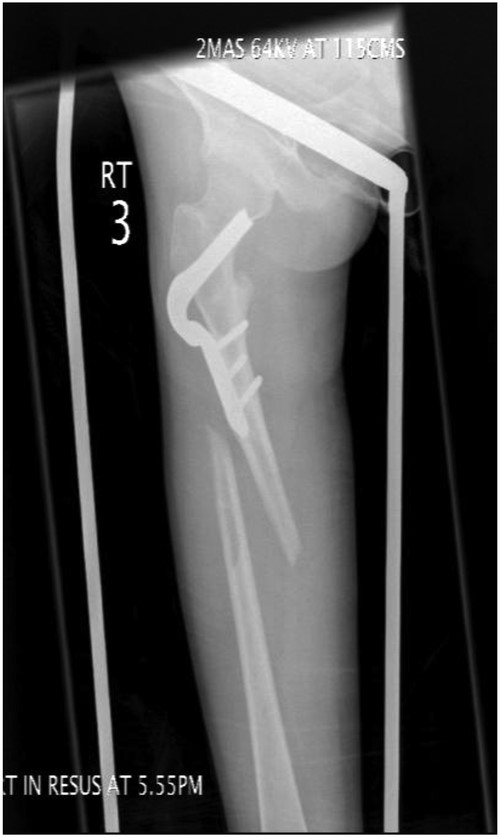

An 18-year-old female with a history of quadriplegic cerebral palsy (GMFCS-V) was admitted to our orthopaedic department following a peri-prosthetic fracture of the right femur. She is well known to our department, as her non-ambulatory status has resulted in a number of surgeries including a right adductor tenotomy, aged 11, femoral derotation osteotomy and dega acetabular osteotomy, aged 13 and right distal hamstring and knee capsule release, aged 14. She presented to the emergency department with a painful right thigh after getting her leg caught in doorway while being mobilized in a wheelchair. The trauma resulted in lateral bending of the leg, with examination revealing a significant deformity of the thigh with audible crepitus. Radiographs revealed a peri-prosthetic fracture of the right femoral shaft extending distal to the AO blade plate (Fig. 1). The blade was also seen to be encroaching on the inferior cortex of the femoral neck leading to concerns about creating a stress riser or femoral neck fracture in the event of revision blade plate fixation. There was also concern that the longest replacement blade plate available would not be of sufficient length to stabilize the fracture distally. The complexity of this case along with the patients low body weight (26 kg), small skeletal morphology and underlying neurological disorder deemed revision with a long-blade plate, or standard adult femoral fixation devices unsuitable. Therefore, we proposed a long PHILOS™ proximal humeral locking plate (Synthes, UK) as a suitable device for internal fixation of the fracture to provide adequate plate osteosynthesis, with secure proximal and distal fixation, bridging the fracture and the femoral neck defect.

AP-XR demonstrating a peri-prosthetic fracture of the right femur below the blade plate. Blade plate noted to be breaching femoral neck.